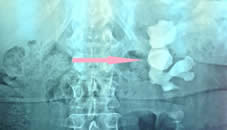

Κάποτε, λόγω του μεγάλου μεγέθους του λίθου χρειάζονται περισσότεροι τέτοιοι δρόμοι όπως στις φωτογραφίες.

Αυτή η δυνατότητα είναι πολύ σημαντική σε περιπτώσεις με λίθους σε κάθε σημείο του νεφρού όπως στην φωτογραφία.